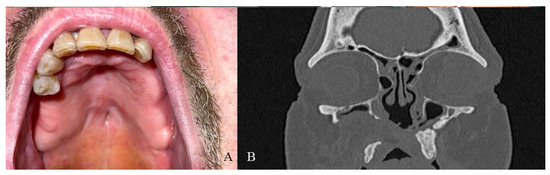

A 52-year-old male patient came to our attention in 2017, presenting with a palatal/oro-nasal fistula measuring 3.5 cm in diameter along the major axis, with atrophic soft tissues surrounding the lesion (Ia according to the Okay et al. classification [14]). The patient had already been treated in 2015 in another center using a palatal local flap with no success and was then treated with an obturator. At the clinical and radiographic examination (Figure 4), a wide oro-nasal communication with exposure of the nasal cavity and septum was observed, leading to speech disturbances, rhinolalia, and eating difficulties.

Figure 4. (A) Clinical presentation of the oro-nasal communication. In inset A, it is possible to appreciate the visibility of the nasal septum. (B,C) Radiographic and 3D reconstruction using InVivo6® and Anatomage Table EDU vers.8® (Santa Clara, CA, USA) software. DICOM files were imported in InVivo6® (Santa Clara, CA, USA) software to obtain the axial, cross, and panorex sections. Afterwards, the DICOM files were imported into Anatomage Table EDU vers.8® (Santa Clara, CA, USA) to obtain the 3D rendering.